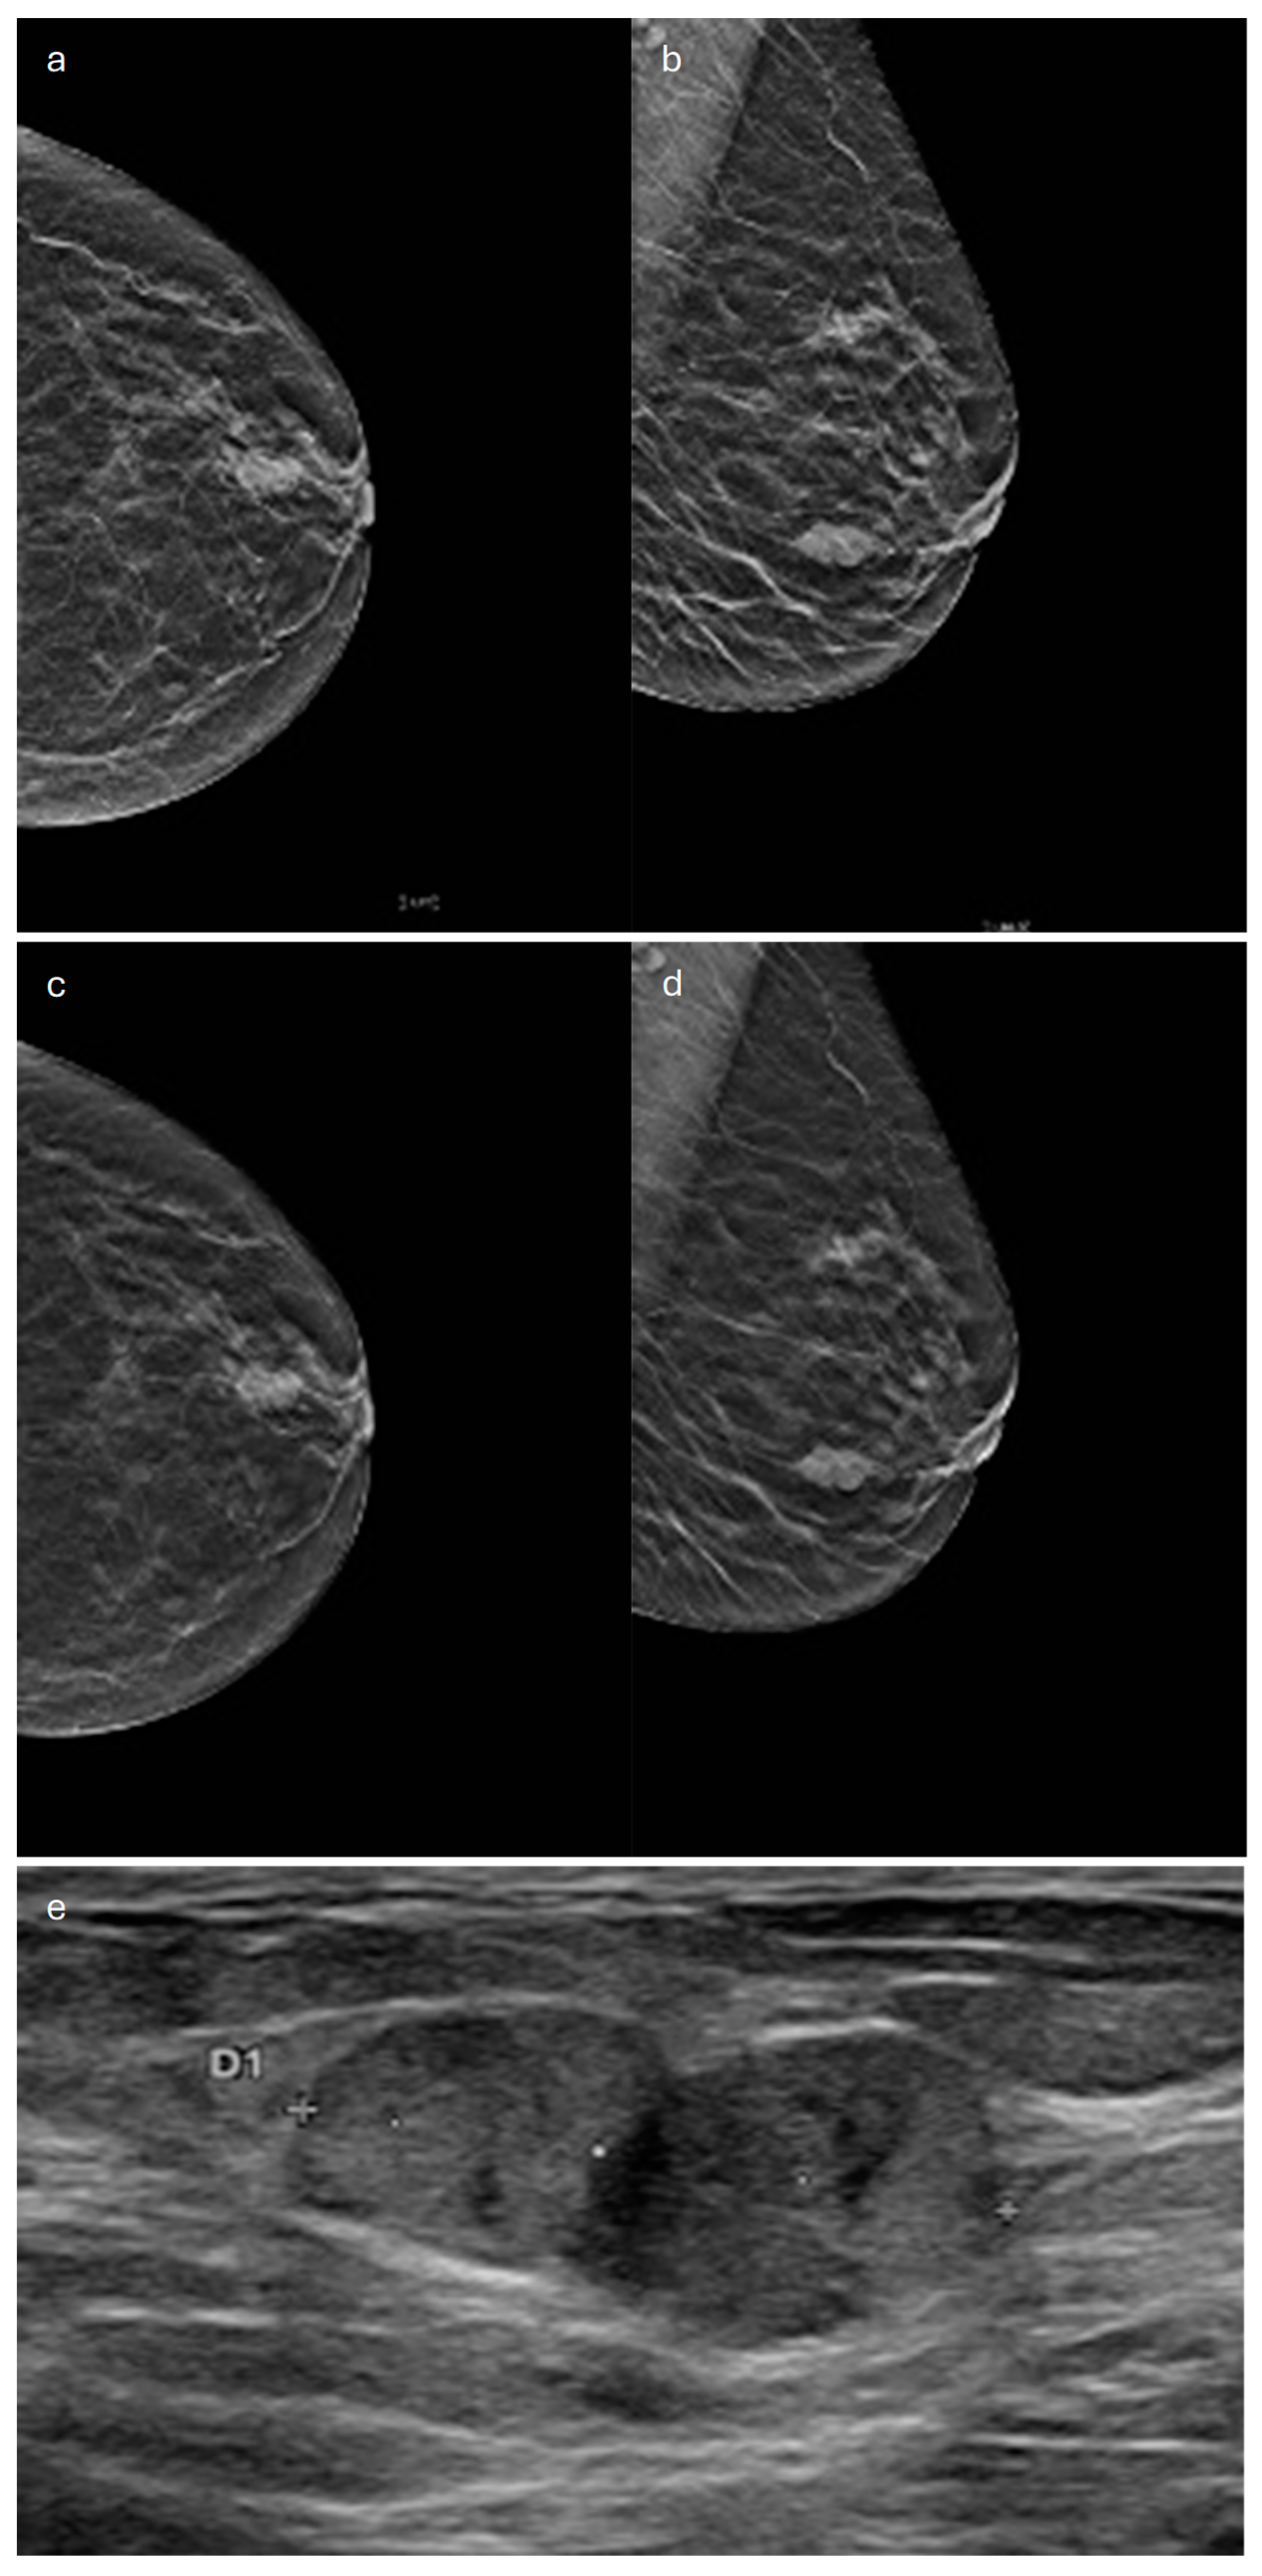

6. Medullary